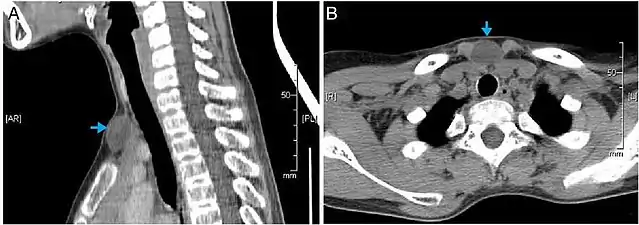

- CT scan, showing a homogenous hypodense volume (unspecific cyst-like)